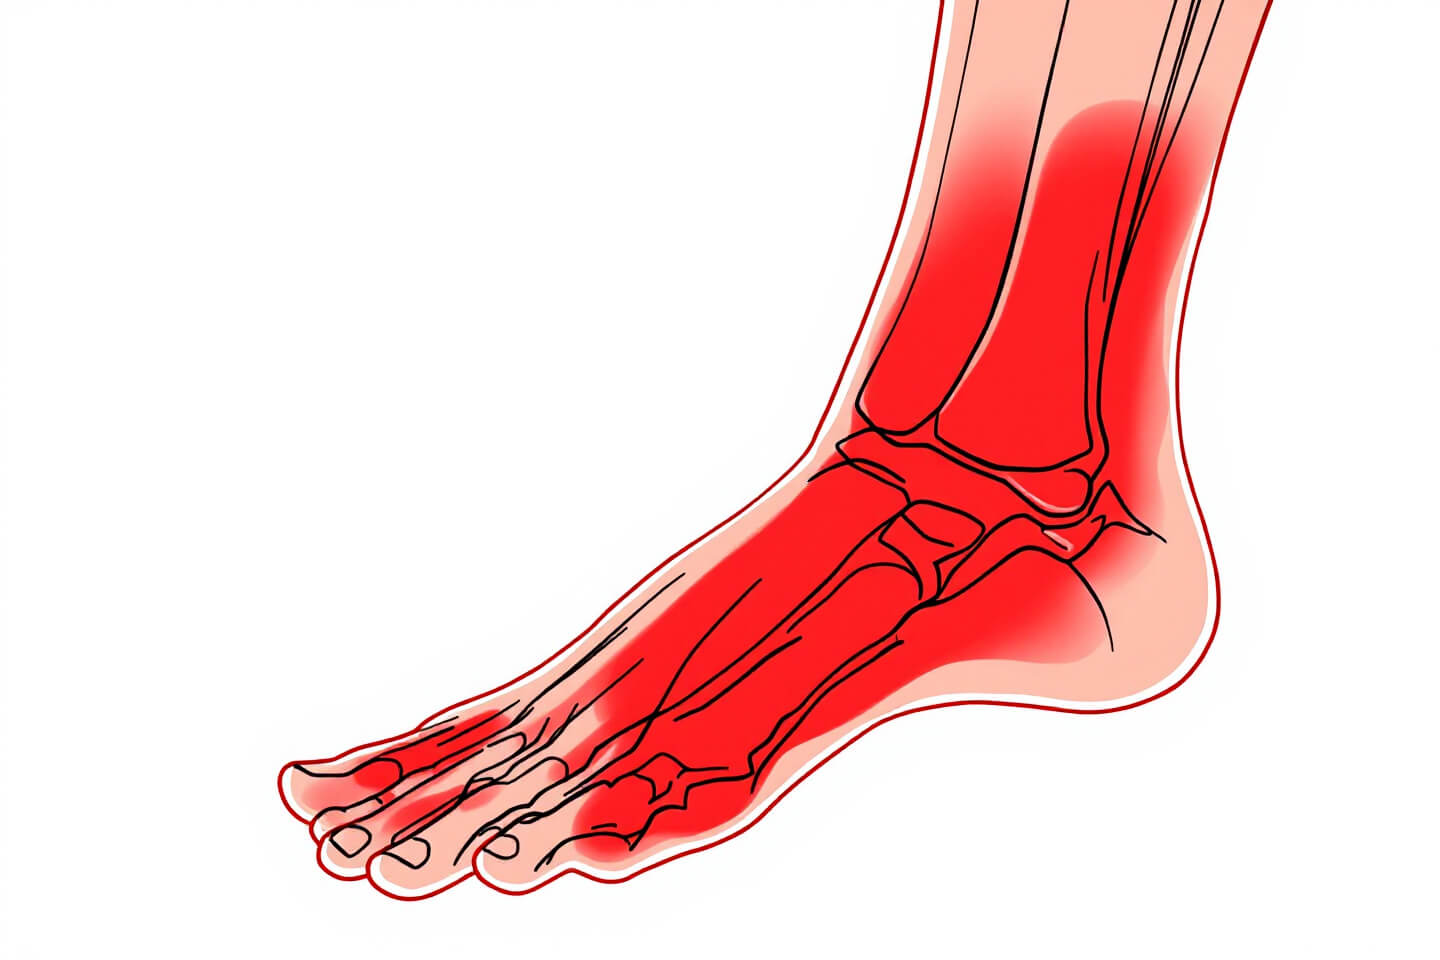

2. 어깨통증의 증상

- 찌릿하거나 둔한 통증: 움직일 때 특히 심해지는 경우가 많습니다.

- 움직임 제한: 팔을 올리거나 회전시킬 때 불편함을 느낍니다.

- 밤에 심해지는 통증: 특히 회전근개 손상 시, 누울 때 통증이 악화됩니다.

- 부종 및 발적: 염증이 있을 경우 붓고 붉어질 수 있습니다.

- 근력 약화: 통증으로 인해 어깨 근육의 힘이 약해질 수 있습니다.